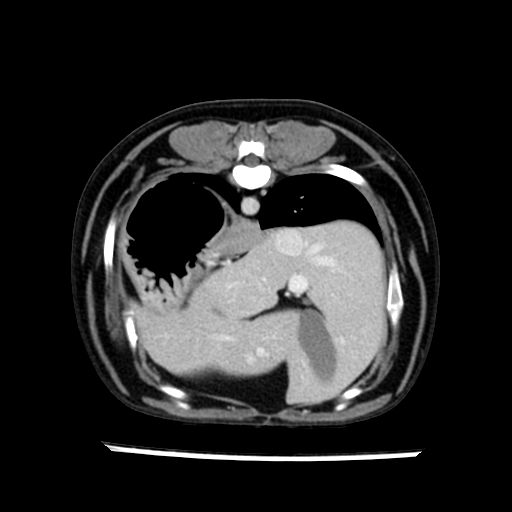

prescritto esame TAC

sequenza immagini limitata al fegato reni e surreni

le immagini ecografiche rispetto alla tac datano circa 7 mesi prima ,le surrenali sono normali nonostante il test acth sia risultato positivo .all’esame TAC dopo diversi mesi risultano aumentate armonicamente nel volume e si individua un forte sospetto di adenoma ipofisario .

sospetto adenoma ipofisario vs. meno probabilmente meningioma della base; intertiziopatia polmonare; lesione espansiva epatica, verosimilmente del lobo laterale sinistro, di sospetta natura neoplastica; lesioni spleniche di natura da definire; iperplasia/ipertrofia delle ghiandole surrenali, bilateralmente; vertebra di transizione del rachide toracico; tenosinovite cronica del muscolo bicipite brachiale di destra.

- Nessuna informazione diversa per quello che riguarda l’esame ecografico del fegato e la presa del contrasto si confermano le lesioni individuate e l’ipoenanchement in fase portale.

- la total body permette di escludere metastasi e di avvicinarsi all’interventistica

la tac dopo 7 mesi permette misure tridimensionali 5,2 x 9,2 x 4,5 cm (forma piu’ allungata )